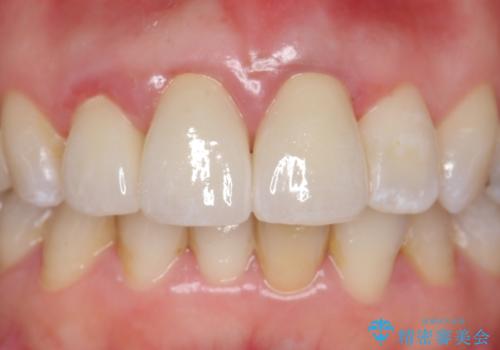

オールセラミッククラウン(スペシャル) 不揃いな前歯を美しく

- 前歯の長さが違うのが気になるといらっしゃった方の症例です。

根尖病変を認めたため再根管治療を行った後、オールセラミッククラウン(スペシャル)にて補綴を行いました。

歯肉の腫れをより改善するため歯周外科を提案しましたが希望されませんでした。